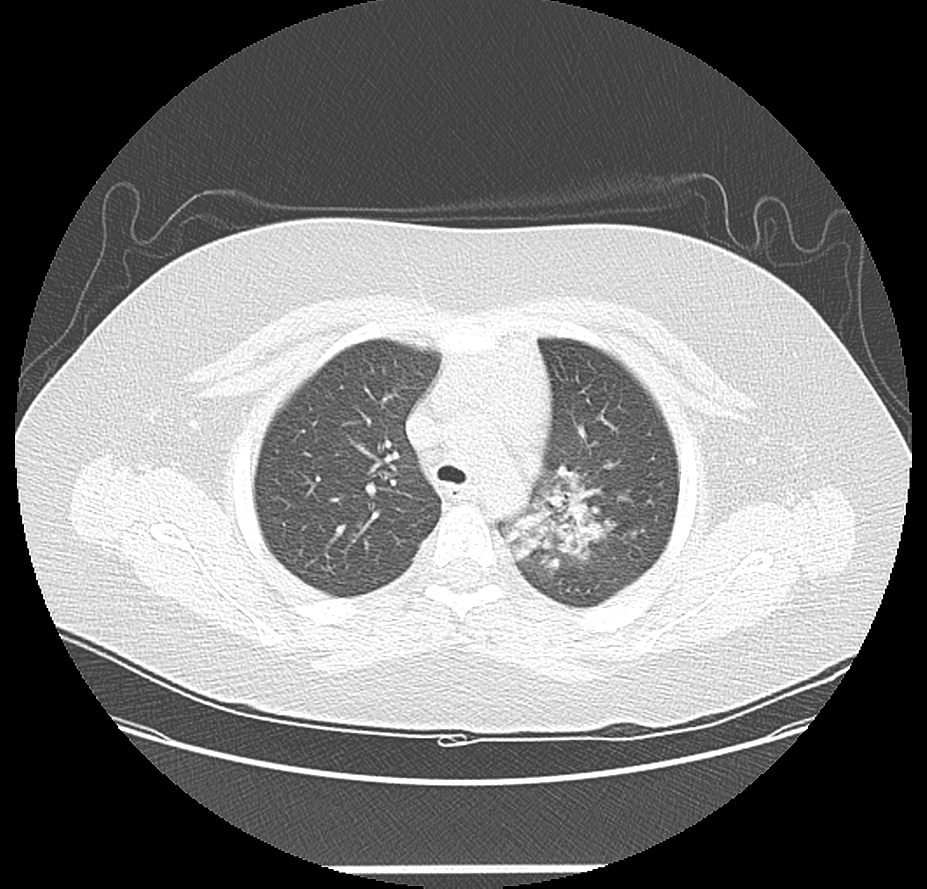

11살 소년

왼쪽부터 오른쪽 상엽으로 퍼진 흉부 X선, 흉부 CT 단면, 종단면